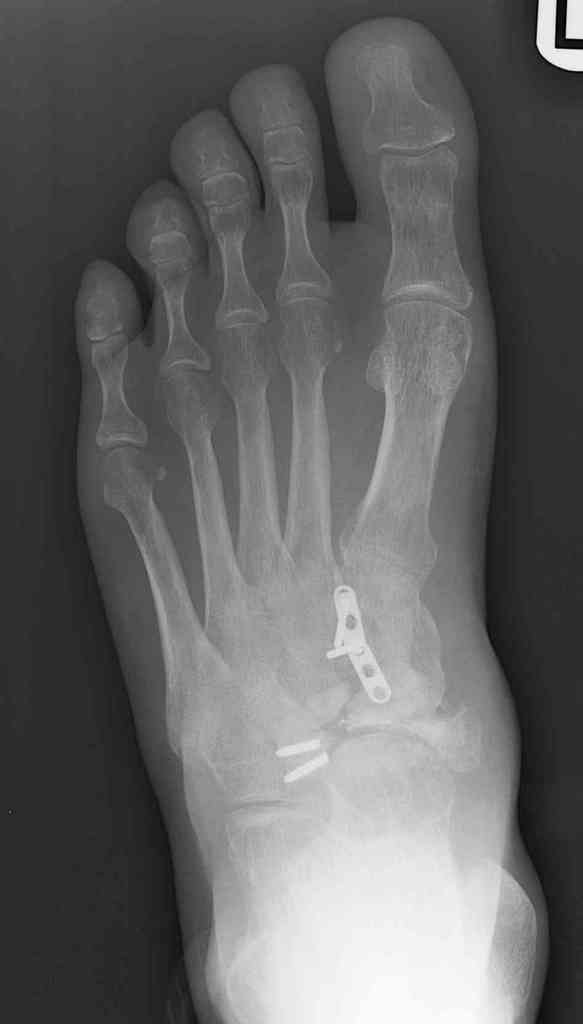

This is a 44 year old male laborer, smoker, who had his foot caught in a forklift about a year ago.

He had an ORIF and subsequent removal of hardware and presented to me with severe midfoot pain. His medial column is grossly unstable on exam but is passively correctable. Wounds are well healed, no sign of infection.

I haven't found much literature on salvage for this. What next? Iliac crest graft for structure with talo-navicular-cuneiform arthrodesis to restore the medial column? Will this fuse as an isolated procedure and given the loss of most of his subtalar motion, would a talocalcaneal arthrodesis improve his chances of fusion?